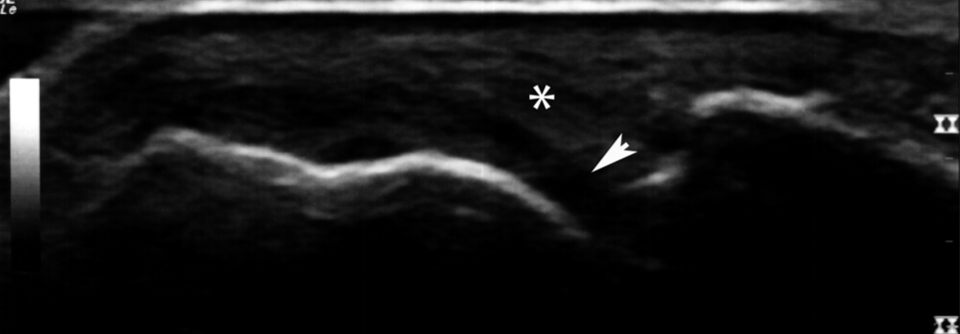

Ein weiterer diagnostischer Baustein ist die Bildgebung. Bei klinischem Verdacht auf eine rheumatoide Arthritis steht beispielsweise eine Röntgenaufnahme von beiden Händen und Füßen an, um für den weiteren Krankheitsverlauf einen Ausgangsbefund zu haben. Besonders wichtig ist zudem die sonografische Darstellung. Erfahrene Schaller können dabei typische Zeichen wie Gelenk­ergüsse, synoviale Proliferationen, Tenovaginitiden oder Erosionen nachweisen.